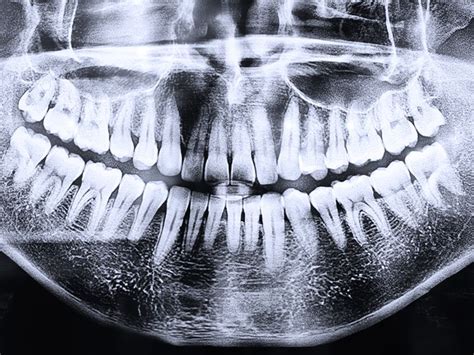

Después de 25 años de actividad profesional continuamos viendo la cara de impacto y sorpresa de los padres cuando ven una primera radiografía de la boca de sus hijos. ¿Pero cuántos dientes hay en la boca? Suele ser lo primero que preguntan. Y es que en la boca de un niño podemos llegar a ver una auténtica multitud, entre los dientes de leche que ya tienen y los definitivos que se están formando y esperan a salir, en el sitio que ocupan los primeros. Pero no siempre ocurre esto, a veces unos se resisten a salir, otros no acaban de caer y algunos se cruzan en el camino que no les corresponde.

Diagnóstico: Radiografía Dental

Para evitar problemas más graves, es recomendable realizar un diagnóstico temprano del caso a través de una radiografía panorámica de la boca. Ante esta evidencia lo único que podemos hacer es revisiones periódicas en las que con una simple radiografía podemos ver y controlar qué está pasando dentro de la encía.

El primer control en niños se recomienda a los 6 años, a esa edad podemos ver los dientes de leche y también todos los que van a salir o que se están ya formando. Con esta información podemos vislumbrar los problemas que va a presentar ese paciente en un futuro.

Estas radiografías se usan con bajos niveles de radiación para capturar imágenes del interior de los dientes y encías. Se suele utilizar para obtener información anatómica general de la boca, principalmente en la primera cita para tener una visión general de la situación del paciente. El TAC dental es la prueba más común en tratamientos de implantes. Además se coloca un delantal de plomo sobre el pecho, abdomen y región pélvica para evitar cualquier exposición innecesaria a la radiación en los órganos vitales. El embarazo es una excepción a la regla. Las radiografías dentales no requieren preparación especial. Cuando las imágenes están listas, al instante en el caso de las radiografías digitales, el odontólogo las revisará y verificará si hay anormalidades o patologías.